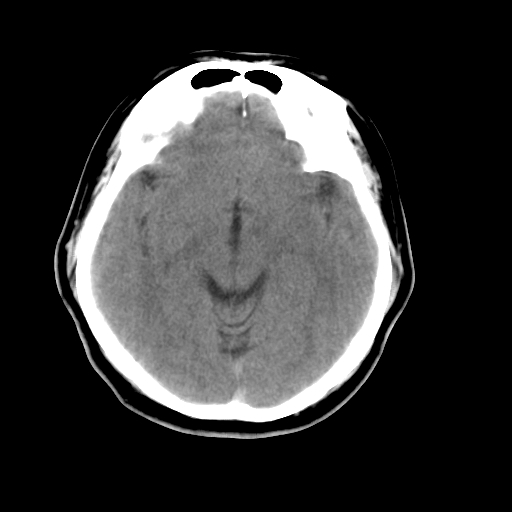

以下是引用liuyue在2008-4-28 13:34:00的发言:[br]右额叶条状高密度影,边缘清楚,周围未见水肿及占位.[br]考虑:血管畸形可能性大.[br]建议:强化ct扫描或mri检查.除外脑回钙化.

以下是引用论黑辩白在2008-4-28 12:53:00的发言:[br]右额叶局限性脑萎缩,右额叶见条状高密度影,建议mri进一步检查。[br][br][本贴已被 论黑辩白 于 2008-4-28 13:08:16 修改过]